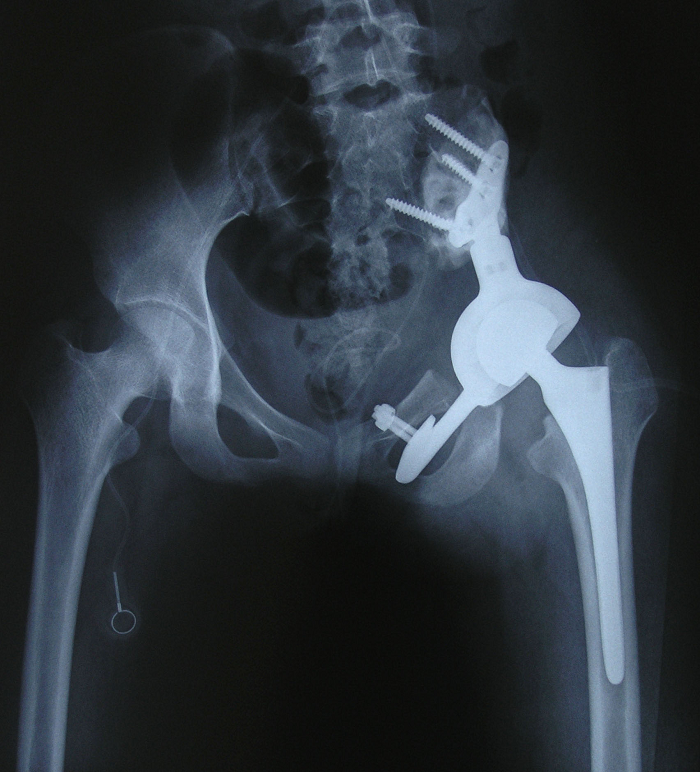

6、病例6:女 18岁 左半骨盆骨肉瘤,全身及肿瘤局部选择性动脉灌注大剂量化疗后行肿瘤切除人工半骨盆假体置换术

图 33 术前X线片

图 34、35、36 术前CT:肿瘤体积巨大,压迫

输尿管、膀胱等盆腔脏器

图 42 术后X线片